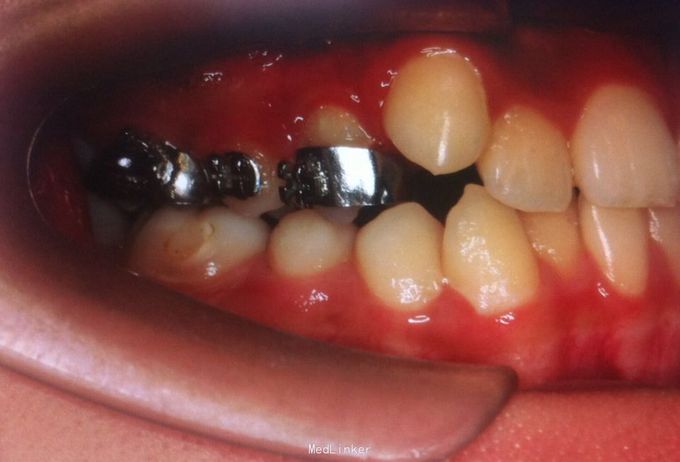

恒牙期 口内见摆式矫治器 左侧磨牙近中关系,右侧中性关系 前牙覆合覆盖正常 中线不正 上下牙列拥挤 张口度正常 关节有弹响 开口型异常